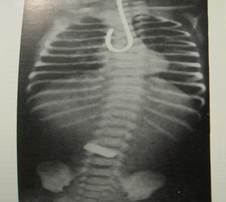

Диагностика классических пороков не сложна, особенно, если нет сопутствующих пороков развития. Есть несколько методов диагностики: зондирование пищевода с помощью тонкого резинового катетера (№ 8-10). Эта процедура должна выполняться в родильном зале. Если это не информативно, через катетер вводят воздух (10-20 мл.) (проба Элефанта), который выделяется через нос и рот. Ребенок должен переводиться в хирургический стационар. Наиболее информативным есть контрастирование пищевода контрастным веществом. Однако введение контрастного катетера под рентгенологическим контролем в верхний отрезок пищевода информативнее (Рис 3).

Рис.3. Введение контрастного катетера в верхний отдел пищевода.

Рис.4. Исследование верхнего конца пищевода водорастворимым контрастом.

Соединение между желудочным сегментом и дыхательной системой обуславливает появление воздуха в желудке и кишечнике, которое обнаруживают во время рентгеноскопии органов брюшной полости. Во время проведения контрастного исследования вследствие попадания контраста в дыхательные пути развивается аспирационная пневмония, поэтому чаще отдают предпочтение исследованиям без введения контрастного вещества.